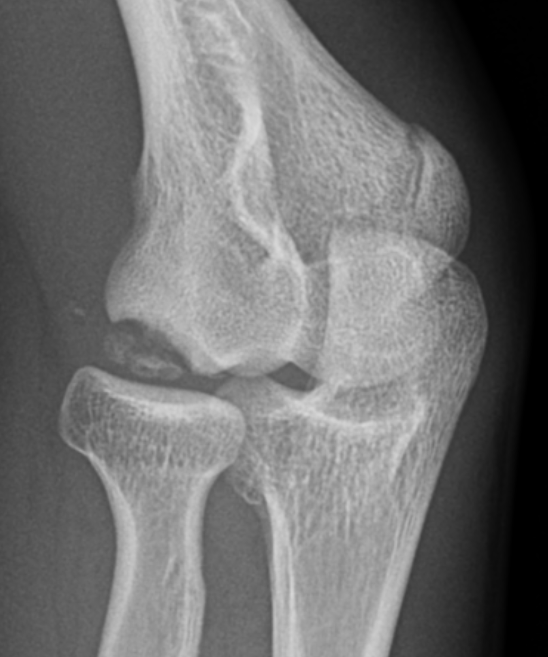

Xray

Kijowski et al Skeletal Radiology 2005

- 50% of capitellar OCD not identified on xray

Localized flattening and translucency Lucency in capitellum